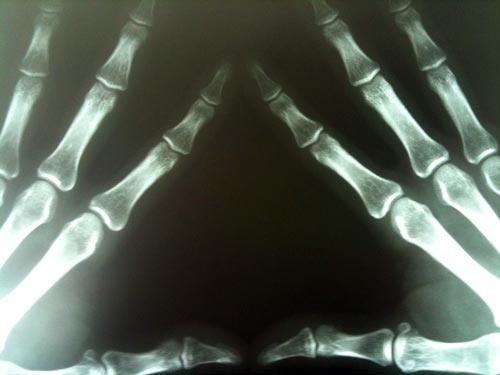

Вильгельм Рентген, Нобелевская премия по физике 1901 года за «открытие замечательных лучей, названных в его честь»

Немецкий физик, вторая буква в фамилии которого, кстати, читается как «ё», стал первым лауреатом Нобелевской премии в этой дисциплине. «Икс-лучи» Вильгельм Рентген открыл незадолго до этого, в конце 1895 года, но их исключительное значение стало очевидно сразу и всем – так, кстати, очень редко бывает.

Излучение, свободно проходящее сквозь мягкие ткани, хуже через плотные и почти полностью задерживаемые твердыми, стало абсолютно незаменимым средством диагностики в травматической хирургии и применяется во многих других областях. К чести этого великого подвижника, он отказался патентовать свое изобретение, заявив, что оно должно быть общедоступным.